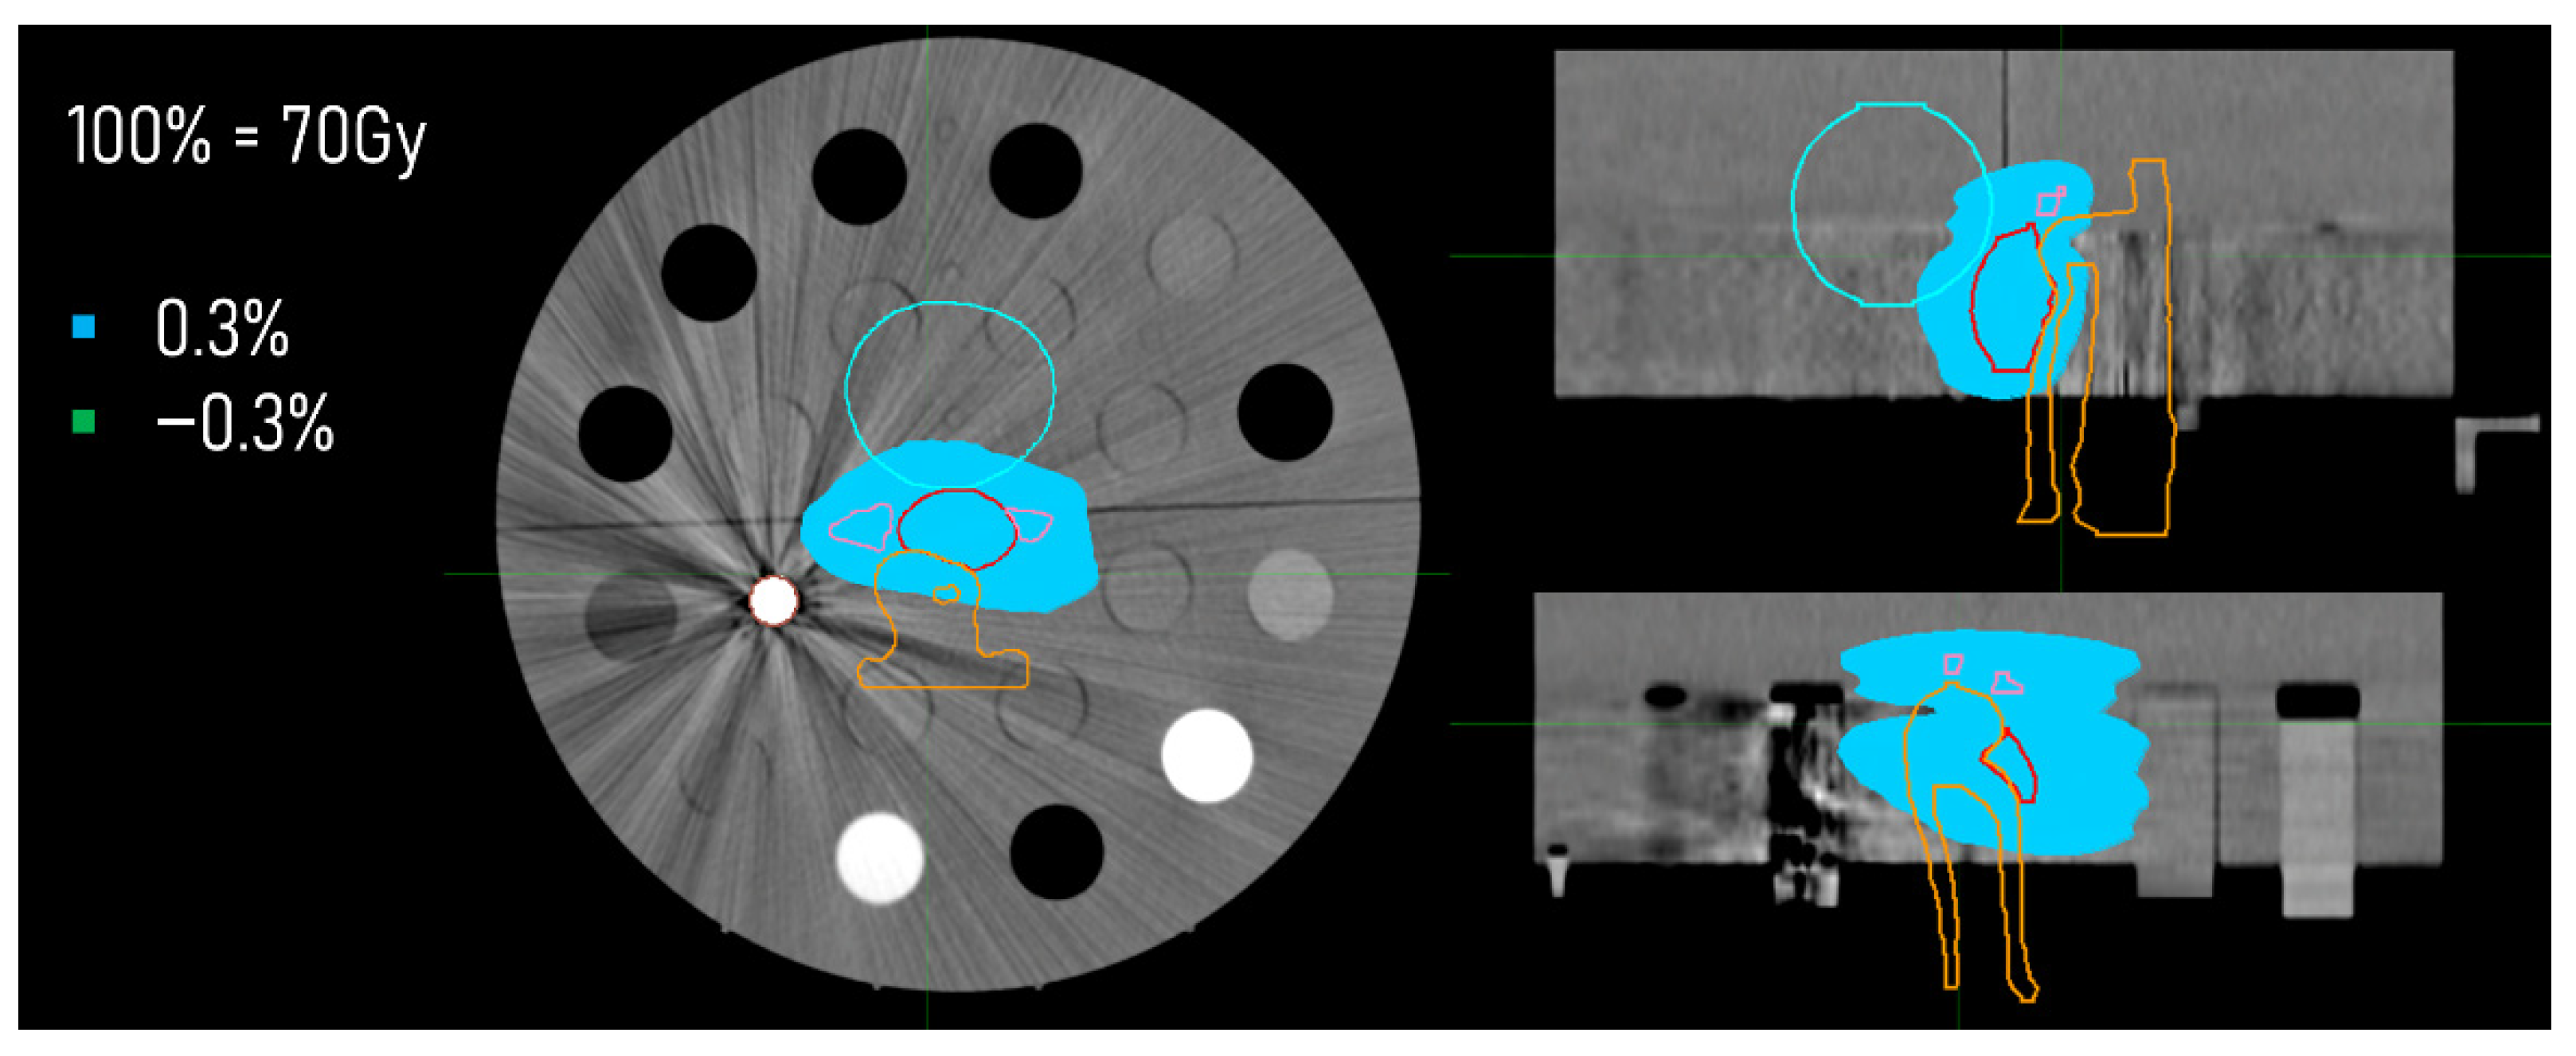

3.3. Dose Distributions